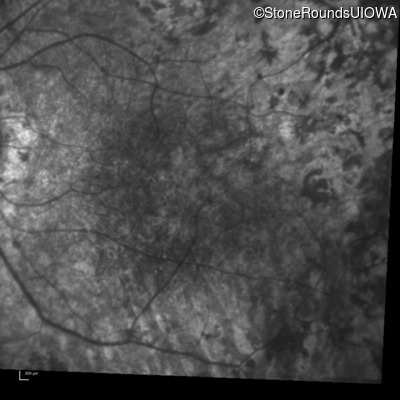

Infrared Fundus Photograph - Right - 20/150

Exemplar